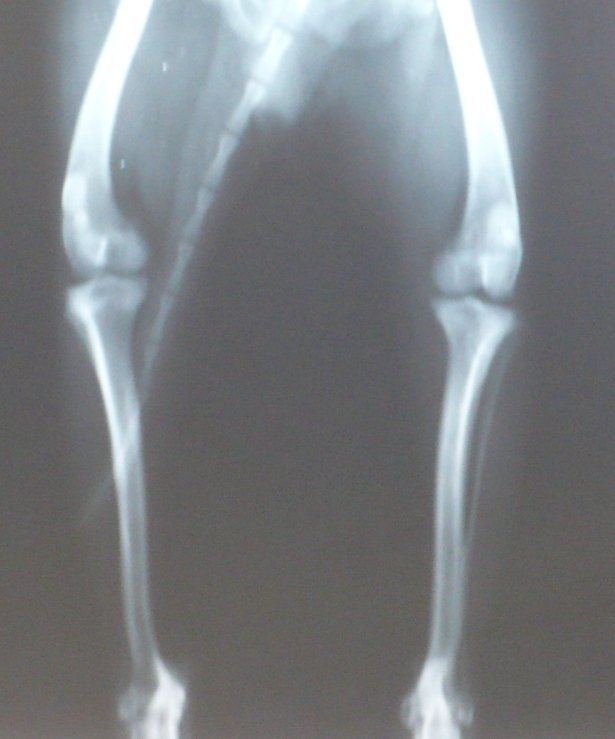

Вот снимок с разным увеличением суставов Микуши. yamagutti, обратите, пожалуйста, внимание и на скакательные суставы, хоть их и мало видно

• 1_1.JPG

Чихуахуа (1.JPG)

169,1 KB · Просмотры: 201

• 1_2.JPG

Чихуахуа (2.JPG)

238,2 KB · Просмотры: 206

• 1_3.JPG

Чихуахуа (3.JPG)

246,3 KB · Просмотры: 208

• 1_4.JPG

Чихуахуа (4.JPG)

299,4 KB · Просмотры: 214